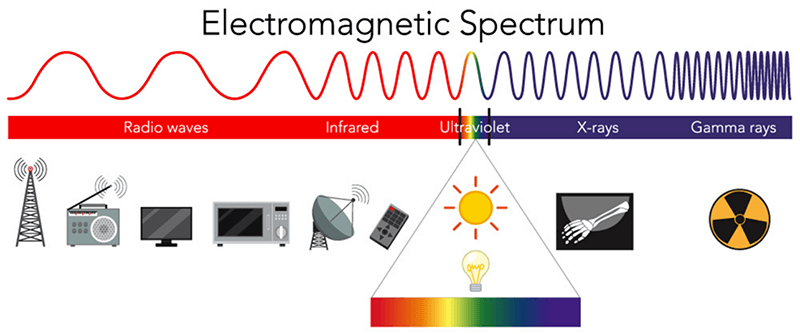

MRI stands for Magnetic Resonance Imaging. In its early days, MRI was referred to as NMR, Nuclear Magnetic Resonance, because of its dependence on the nuclear structures of an atom. Many confused this with a negative connotation associated with the word Nuclear, so that word was dropped. As we will learn later, MRI does not use ionizing radiation at all in the collection of data and creation of an image. MRI does use radiation, in the form of radiofrequencies, but it is not ionizing, which means it cannot cause cellular damage like x-rays and radionuclides.

Radiofrequencies are part of the electromagnetic spectrum. They are found on the low energy end of the spectrum, far below ionizing radiation. Recall that energy is related to frequency directly: the higher the frequency, the higher the energy level. The higher the energy level, the higher than likelihood of ionizing the atom. You may here it said that MRI does not use radiation at all. A more truthful statement would be that no IONIZING radiation is used.

When the hydrogen protons are introduced to the magnetic field, the dipoles of the protons will align to the magnetic field. It is the RF energy that is applied to the protons in order to disturb them. The radiofrequency used must be at the same frequency as the frequency of the spinning hydrogen proton. Recall I said earlier, all protons spin at different frequencies at which they spin. We will get into more detail about this later, but for now just know these facts.

As mentioned earlier, we need all three things. The strong magnet, the protons and the RF. If the RF was taken away, the protons would simply stay aligned to the magnetic field. It is the disruption of the protons that will ultimately create the signal measured during an MRI examination.

There are 3 requirements to obtain an MRI Image: A strong magnet, an abundant atoms with an odd number of protons, and a radiofrequency which is a non-ionizing form of radiation.